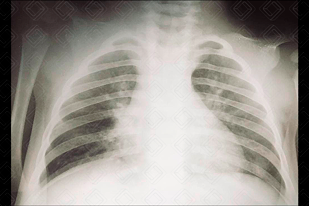

Texto alternativo para a imagem Figura 2. Créditos: Dra. Elazir Mota - Rio de Janeiro/RJ

Descrição da figura 2: Radiografia de tórax evidenciando sinais de hiperinsuflação do pulmão direito. Observe que a transparência pulmonar neste pulmão se encontra aumentada em relação ao contralateral e com a trama vascular reduzida, sugerindo hiperaeração deste parênquima. A causa foi aspiração de milho de pipoca.

• Radiografia de tórax: A radiografia de tórax pode ser normal, mas em boa parte dos casos apresenta sinais indiretos: hiperinsuflação pulmonar do lado acometido ou pode haver a presença de alguma opacidade pulmonar (atelectasia) . Na maioria dos casos, o corpo estranho causa uma obstrução parcial do brônquio, funcionando como mecanismo valvular, ou seja, o ar entra e tem dificuldade para sair, levando a hiperinsuflação. Já nos casos de obstrução total, observaremos atelectasias ( figuras 1 e 2 ) ;